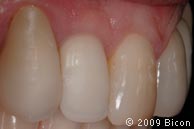

66. Вид интегрированной коронки (IAC).

67. Вид интегрированной коронки (IAC).